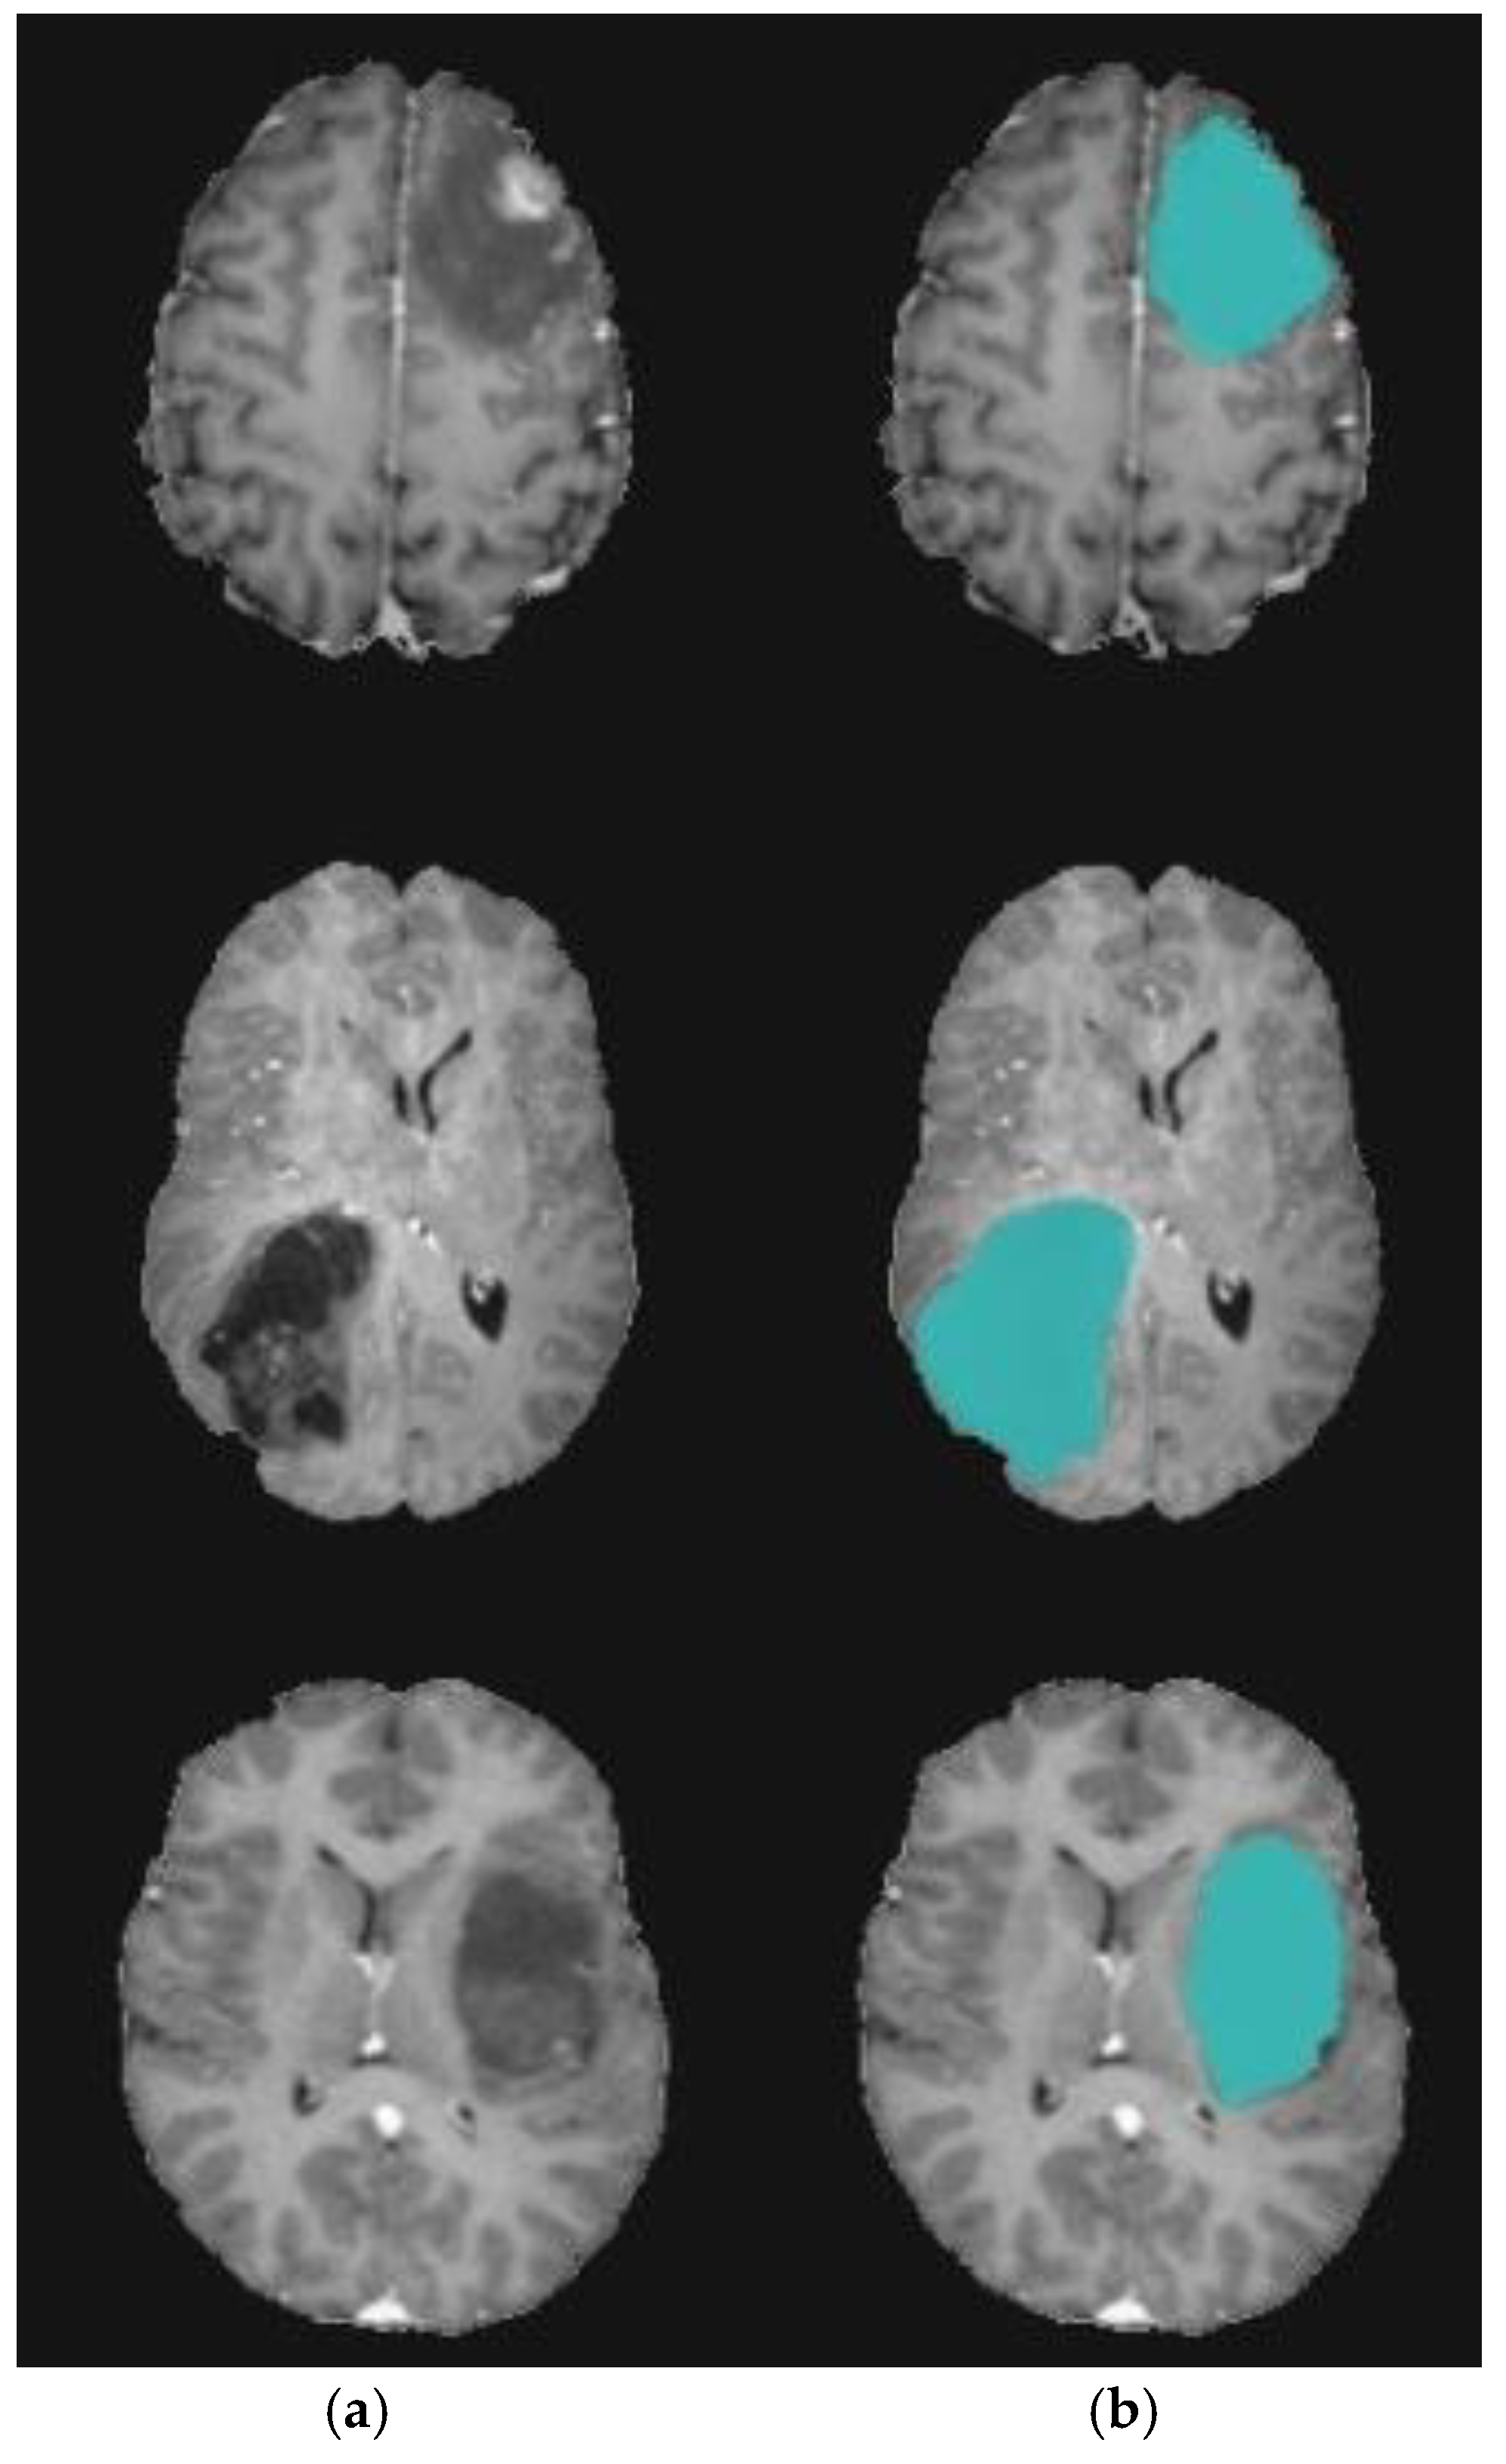

4.3. Experiment 3: Role of DA to Reduce Level Set Iteration

The goal of this experiment was to emphasize the role of DA in reducing the level-set segmentation iteration number. Herein, to reduce time cost and increase accuracy, the initial contour of the region of interest (ROI) target was automatically generated based on the two-step DA clustering result. Table 5 shows the comparative results of the suggested model and traditional level set segmentation algorithms in terms of the number of iterations required for level set to complete the segmentation process. These group of experiments were conducted 10 times to ensure the robustness of the proposed model against random factors, which may affect the stability of the algorithm. Herein, five MRI volumes were randomly chosen. It can be inferred that utilizing the DA algorithm reduces the number of level set iterations dramatically. Using the best-designed two-step DA parameters, the contour was positioned very close to the tumor region. Figure 10 and Figure 11 show a sample of the segmentation process using the modified level set.

Figure 10.

Brain tumor segmentation for BRATS 2017 dataset. (a) 2D slice. (b) Final segmentation with the modified level set.

Figure 11.

Brain tumor segmentation for BRATS 2017 dataset. (a) 2D slice. (b) Final segmentation with the modified level set. (c) Ground truth.